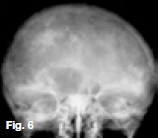

Figures 1, 2, & 3 show a mixed radiolucent/opaque lesion affecting the maxilla, crossing the midline in an edentulous patient, causing flattening of the palate. A lateral skull radiograph of another patient (Fig. 4) shows osteoporosis imperfecta in the posterior and anterior parts of the skull (green arrows) along with thickening of the calvarium and cranial vault which are cardinal radiological signs of the condition. Figures 5 & 6 illustrate "cotton wool" radio-opacities in the skull and the base of the skull shows dense sclerosis. All the images mentioned so far are typical features of Paget's disease. Sir James Paget, surgeon and pathologist who is best remembered for naming Paget's disease. The disease is idiopathic and can be divided into three stages: initial bone resorptive phase, vascular phase with osteoblastic repair, and approximal/ sclerosing phase. The jaws are involved in approximately one in Ave cases, with the maxilla being affected about twice as frequently as the mandible. During the initial phase of bone resorption, the affected bones may be deformed or painful, particularly the weight-bearing structures such as the long bones of the legs (Fig. 7A & B). Later the affected bones expand, commonly in the maxilla, mandible or cranium. At this stage, the dental patient who wears full dentures may complain that the fit of the dentures is becoming progressively poorer. When the maxilla is affected, the alveolar ridge widens and the palatal vault can flatten (Fig. 2). When teeth are present, they may become increasingly spaced, with extensive jaw enlargement. Neurologic complaints can result from increased deposition of bone in the areas of the foramina of the skull causing headaches, auditory disorders progressing to deafness, visual disorders progressing to blindness, facial paresis, and vertigo. The bones are relatively brittle; hence, fractures are likely. Generalised radiolucency/osteoporosis intermediate stage with mixed radiolucency/radiopacity, "driven snow" coarse trabeculation, "cotton wool" radio-opacities in the final stage (Figs. 5 & 6). Hypercementosis, loss of lamina dura, obliteration of the periodontal ligament spaces (Fig. 8) and external root resorption (Fig. 9) may also be present. The upper hand wrist radiograph (Fig.10) of another patient shows the disease affecting the phalanx of the third digit.